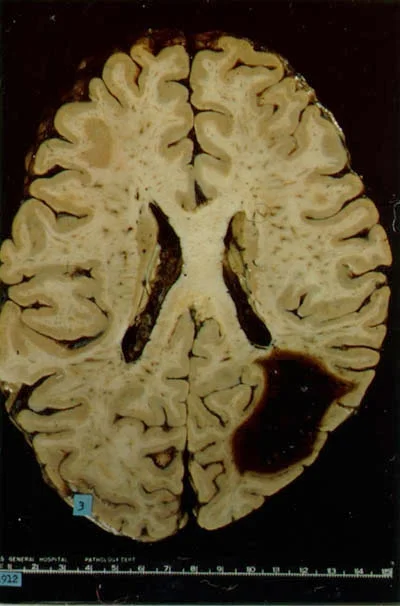

The image to the right is a section of the brain at autopsy in a patient who died after a CAA-related bleeding stroke. The dark area in the lower right has been destroyed by leakage of blood into the brain.